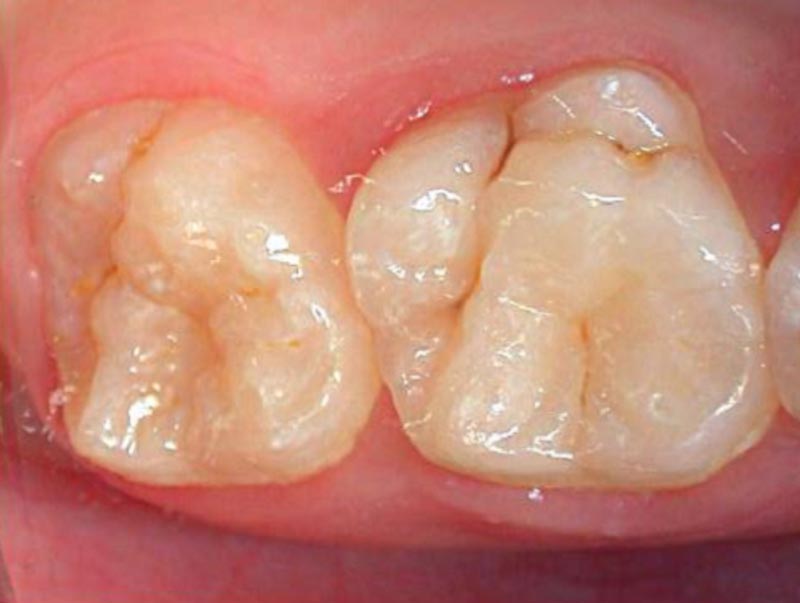

• Fissure sealants1

Fissure sealants BEFORE